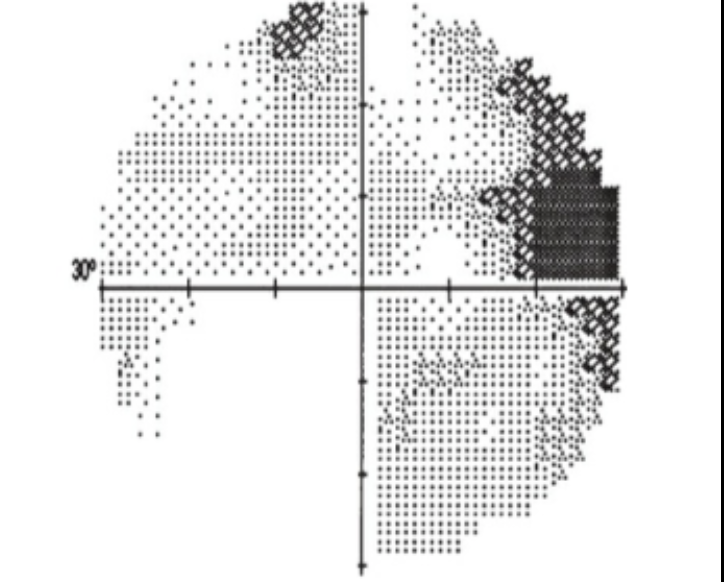

Tons de cinza - Gráfico em escala de cinza que deriva do gráfico numérico. Quanto menor a sensibilidade, mais escuro o tom

O que representa o gráfico total deviation?

Sensibilidade ponto a ponto do paciente - Sensibilidade esperada para indivíduos normais da mesma idade (baseado no banco de dados do aparelho)

Áreas com defeito de campo apresentam valores negativos

O gráfico total deviaton gera um gráfico de probabilidades que mostra a chance daquele defeito encontrado ser encontrado em um indivíduo normal